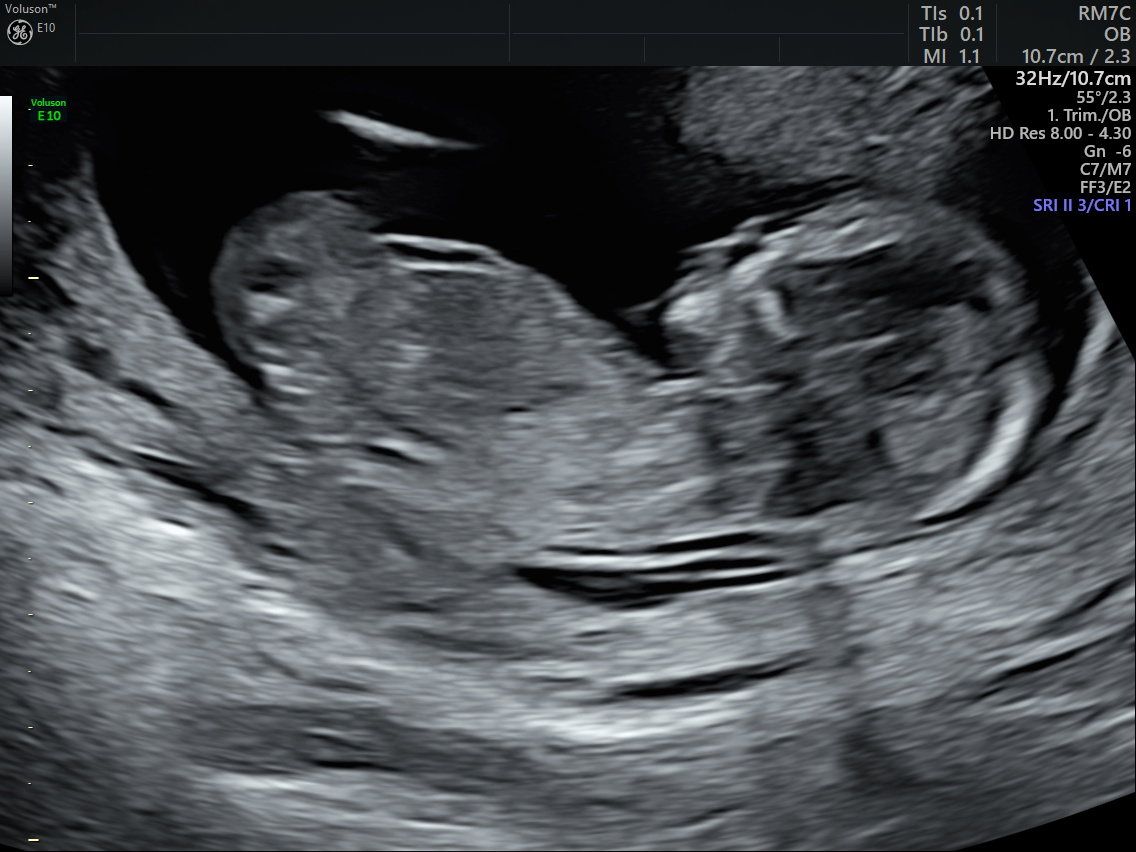

Da du fleißig wächst sind wir natürlich regelmäßig zum Arzt gegangen, um dich sehen zu können und um zu schauen, ob es dir gut geht. Hier warst du ca. 8 cm groß, 30 g schwer und ich in der 14. SSW schwanger. Zu dem Zeitpunkt haben wir auch schon allen in der Familie gesagt, dass du bald kommen wirst. ❤️